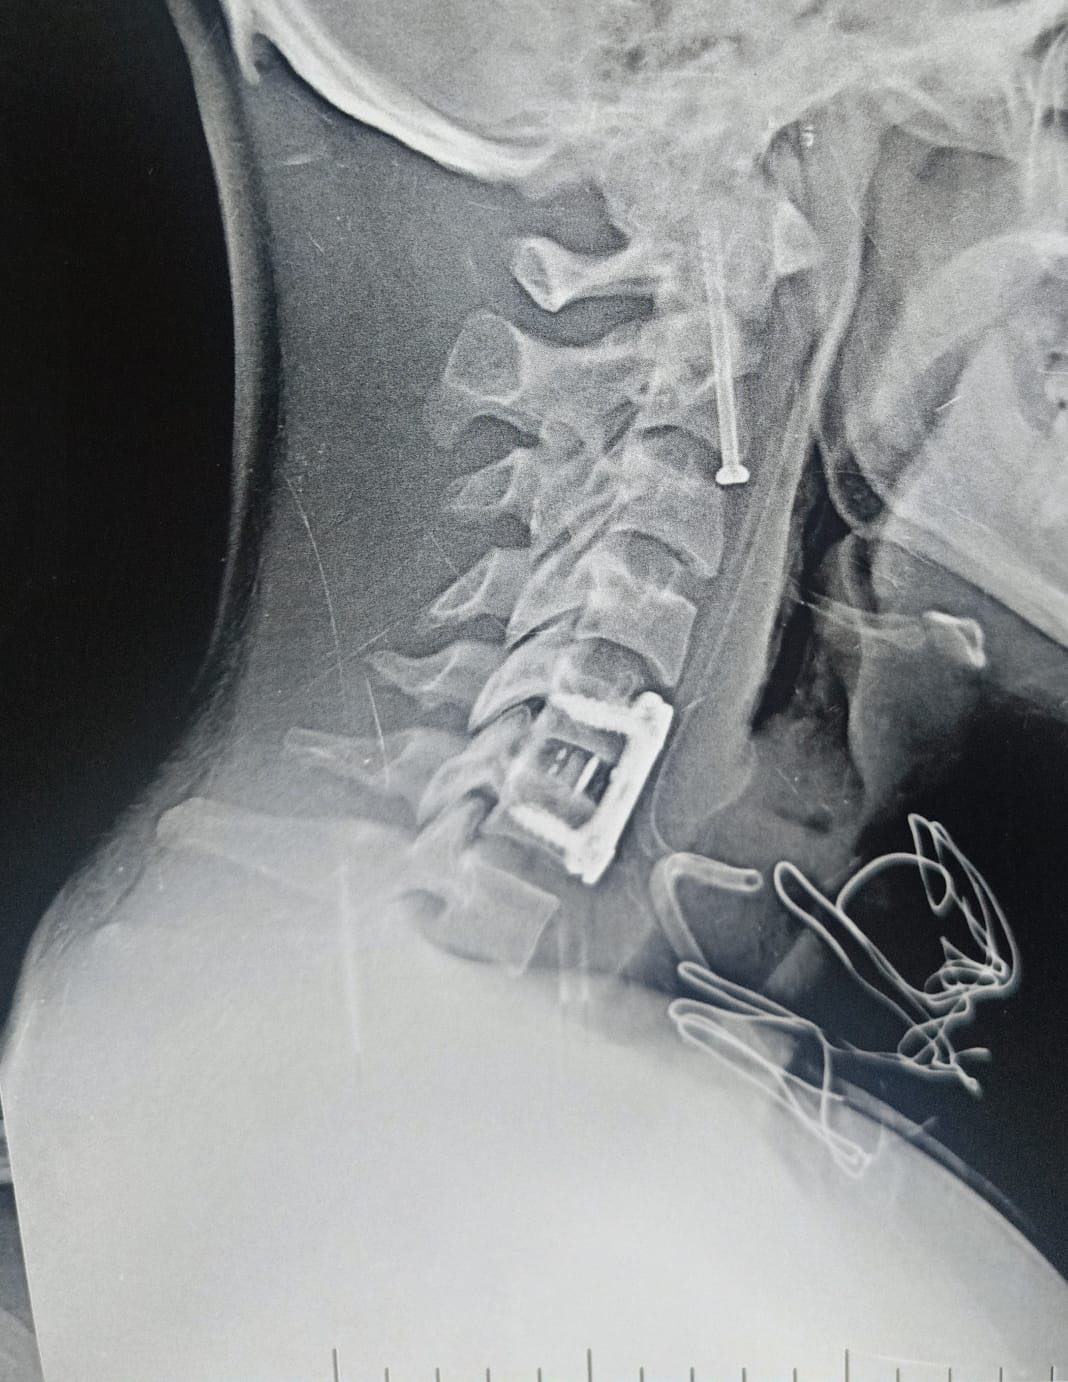

وكان قسم الاستقبال والطوارئ بمستشفيات جامعة بنها قد استقبل المريض عقب سقوطه من علو، وبالفحص والأشعة تبين إصابته بكسر في الفقرة العنقية الثانية، وهي من أكثر المناطق خطورة لقربها من جذع المخ المسؤول عن الوظائف الحيوية، إضافة إلى وجود تزحزح فقاري بين الفقرتين الخامسة والسادسة.

وأُجريت الجراحة تحت إشراف وتوجيه الدكتور إسلام أبو الفتوح رئيس قسم جراحة المخ والأعصاب، والدكتور إيهاب سعيد رئيس قسم التخدير، حيث تمكن الفريق الطبي من تثبيت كسر الفقرة العنقية الثانية بدقة عالية، إلى جانب تثبيت التزحزح الفقاري بين الفقرتين الخامسة والسادسة باستخدام شريحة ومسامير وقفص عنقي.